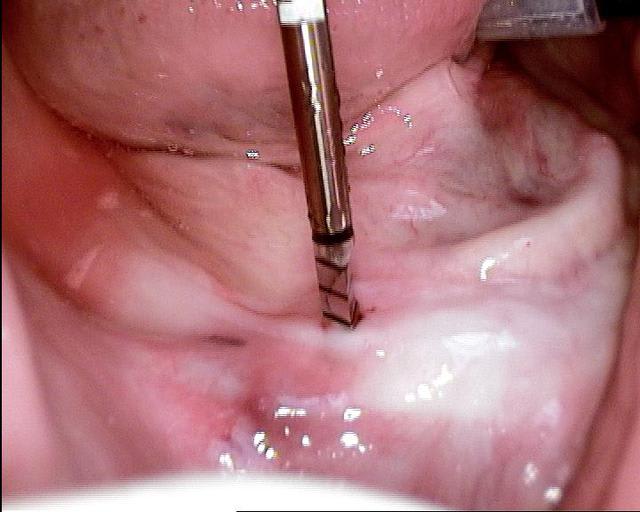

Un cas qui va sans doute prêter à discussions, juste pour montrer que la technique MIMI (non invasive) peut donner des résultats de qualité et esthétiques en moins de temps qu une chirurgie dite traditionnelle.

Les deux premières photos montrent le cas d´une jeune femme ( qui malheureusement s est fait retiré toutes les dents à l´étranger....).Ce cas a pu être terminé deux semaines après l´implantation.

Les forets utilisés ont 3 faces et sont coniques (250 trs/min) permettent une condensation de l´os et un traitement minimalement invasif.